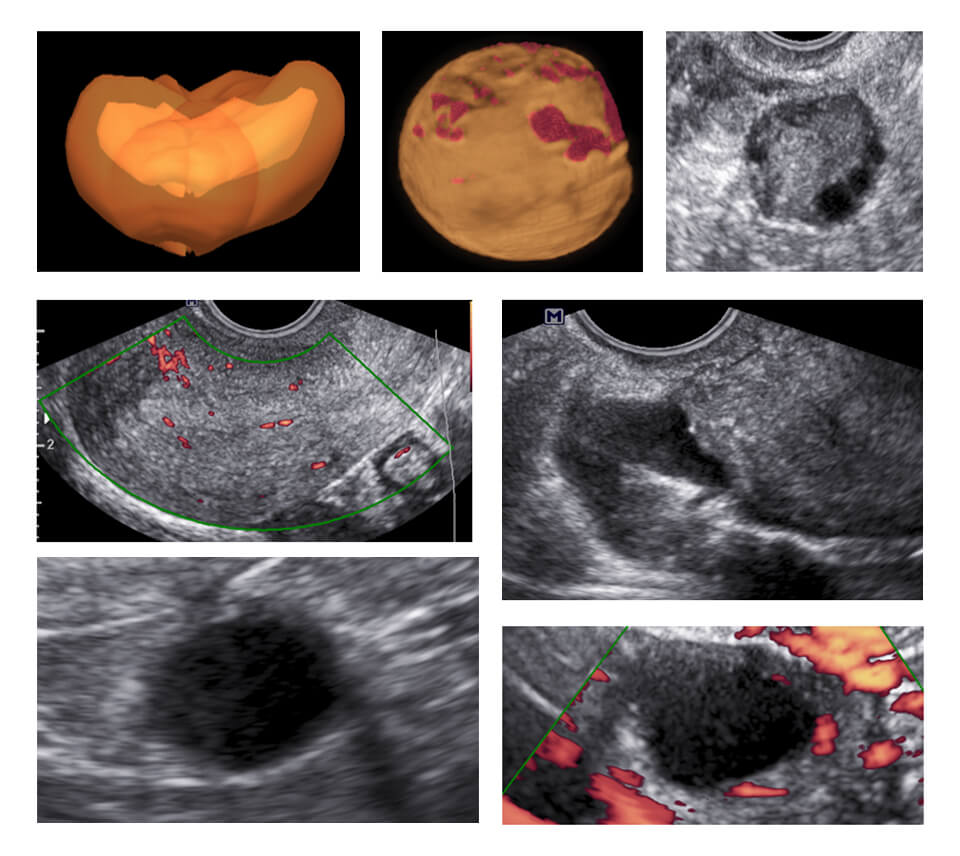

MODULE 2 :- GYNECOLOGY

NORMAL AND ABNORMAL : UTERUS (ENDOMETRIUM/MYOMETRIUM/ JUNCTIONAL ZONE), NORMAL AND ABNORMAL : ADNEXA (ENDOMETRIOSIS/ SIMPLE CYST/ PCO/ DERMOID/ MALIGNANCY), SCORING SYSTEMS IN GYNECOLOGY (MUSA/IDEA/IETA/IOTA)